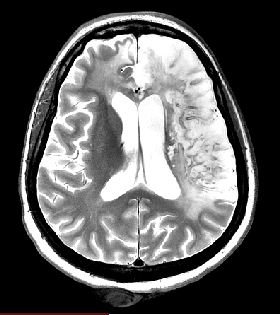

1-2-2 Pathologies lésions

1-2-2-1 Accidents Vasculaires Cérébraux

sujet12211_T2